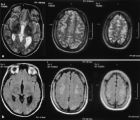

根據臨床表現症狀、體徵可選擇做B超、X線、心電圖、腦電圖、CT等檢查。